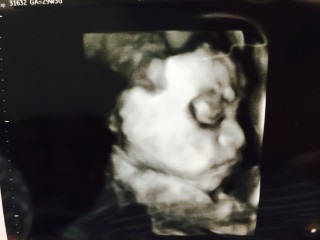

写真:29w3d:りなさん:チラ見?

29w3d♡1451g♡第二子ですが上のお兄ちゃんとは10歳差!男の子です^^日々順調に成長中~♡♡